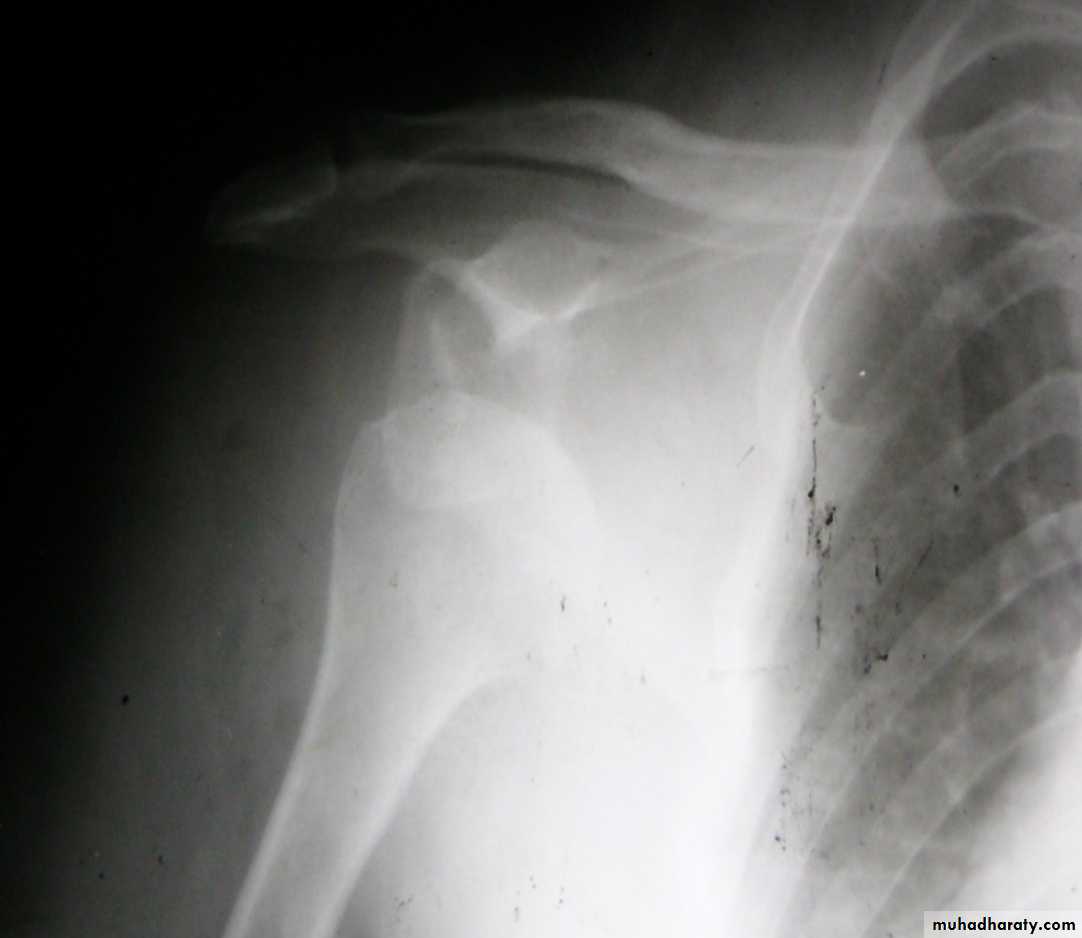

Slide 201- What is the diagnosis ?2- What is the most common early neurological complication ?